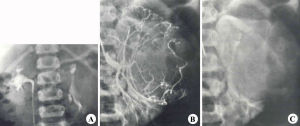

影像檢查是重要診斷手段,靜脈尿路造影仍然是一重要有效手段,患側腎不顯影或表現為腎內腫塊即患側腎盂腎盞被擠壓,移位,拉長變形或破壞。10%病例因腫瘤侵犯腎組織過多或侵及腎靜脈而不顯影。

如小兒以腹部腫塊就診,應先做超聲檢查,以分辨是實質性抑囊性腫塊,也可檢出下腔靜脈是否通暢,如疑有下腔靜脈瘤栓,應做下腔靜脈造影,如下腔靜脈梗阻,應做上腔靜脈和右心導管檢查。ct可判斷原發瘤的侵犯範圍與周圍組織器官的關係;有無雙側病變有無肝轉移及判斷腫塊性質因腫塊包含成分不同可提示是否為錯構瘤有的作者提出如患側不顯影或有鏡下肉眼血尿應做膀胱鏡及逆行腎盂造影因有報告腫瘤轉移到同側輸尿管,膀胱及尿道mri與ct相比較前者不用對比劑,但價格更昂貴,更易辨別腎靜脈及腔靜脈情況,須積累更多的經驗。

從節約來說,對腎母細胞瘤的診斷,一般僅用超聲和靜脈尿路造影也可診斷,並了解其侵犯範圍,肺是腎母細胞瘤最好發的轉移部位,應常規行胸部x線檢查。對透明細胞肉瘤應做骨掃描而惡性桿狀腫瘤應做頭部ct檢查。